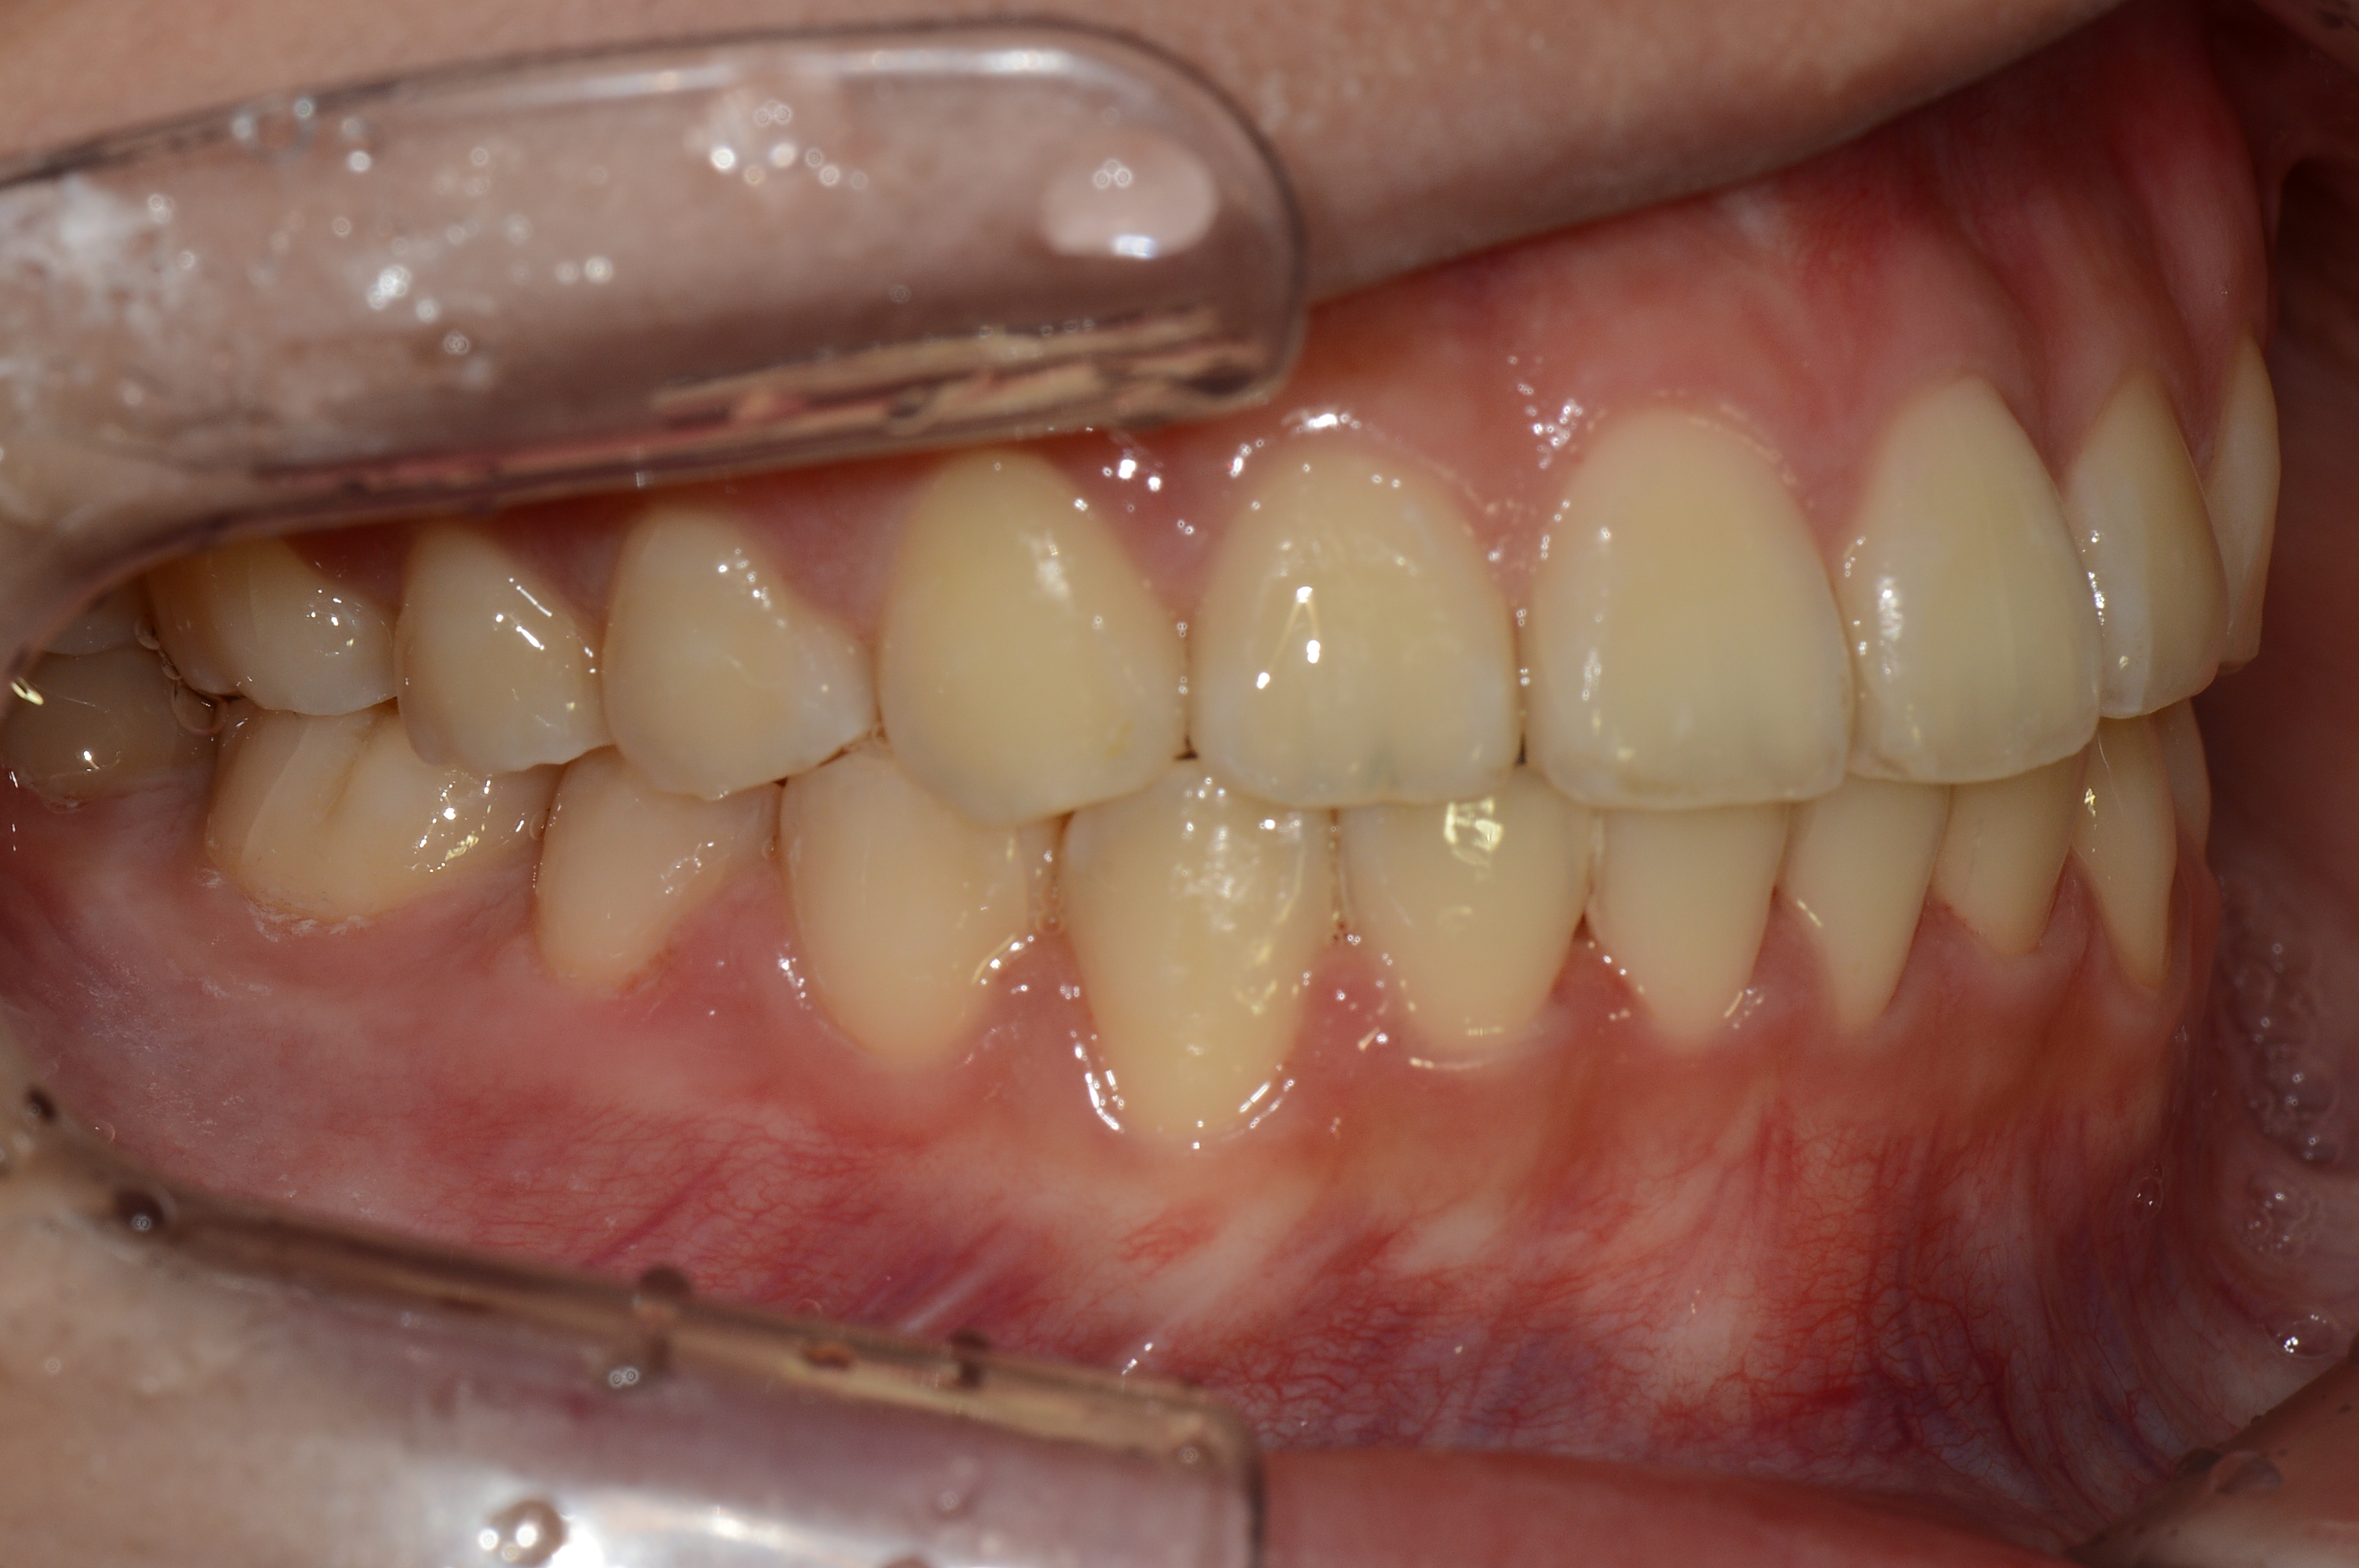

치료 전 사진입니다.